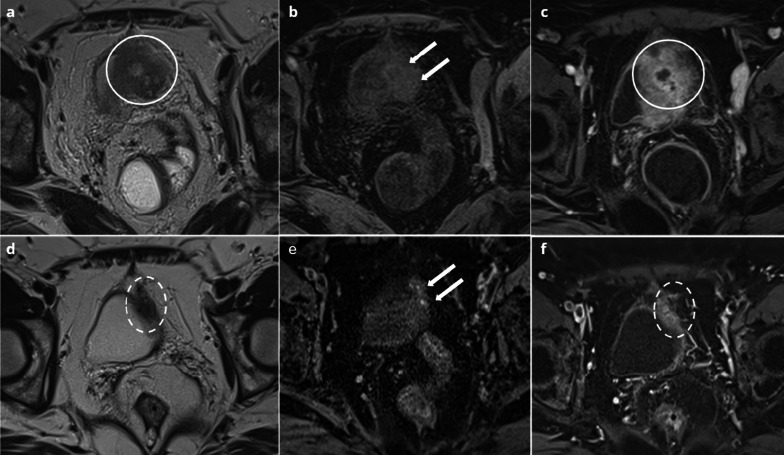

Fig. 3.

39-year-old female with deep endometriosis. Typical endometrioma of the right ovary (arrow): unilocular cyst with shading on T2W images (a) hypersignal > fat on T1W images (b), persisting on T1W FS images (c). Several months later, she presents with pelvic pain, fever and hyperleukocytosis. MRI shows an increase in size of the right endometrioma (arrow), with loss of shading on T2W (d), loss of hyperintensity on T1W FS (e) and a thick, enhanced wall on T1W FS after contrast injection (f)